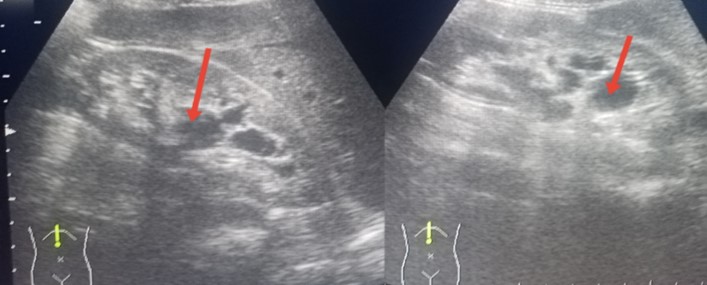

An abdominal ultrasound identified multiple renal cysts, with the largest measuring up to 2 cm (see Figure 2). Ophthalmic examination revealed angiokeratomas on the right eyelid, conjunctival vascular tortuosity, and an aneurysm (see Figure 3).

Figure 2: An abdominal ultrasound showing multiple renal cysts in both kidneys.

2-A: The right kidney with cysts. 2-B: The left kidney with cysts.